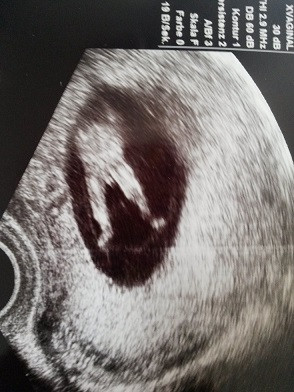

In der 15 SSW kann der Arzt im Ultraschall erkennen, ob die Schwangere ein Mädchen oder einen Jungen bekommt Beim männlichen Baby hat sich jetzt die Anlage für den Penis deutlich herausgebildet. The 15th Waffen SS, together with the 19th Waffen Grenadier Division of the SS (2nd Latvian) formed the Latvian Legion The 15th Waffen SS was swept up in the chaos of the collapse of the Eastern Front and lost much of its manpower fighting in districts surrounding Leningrad (Ostrov, Novosokolniki and Novgorod Oblast). After the unsuccessful Bundestag election in 1961 most of the former DP members left the party;.

SSW) Der Fötus ist in der 15 Schwangerschaftswoche auf eine Größe von beachtlichen acht bis elf Zentimetern gewachsen Die Ausmaße des Kindes sind damit annähernd mit einem Apfel zu vergleichen Das Gewicht des Fötus beträgt in dieser Woche um die 50 bis 70 Gramm Es nimmt gerade ziemlich schnell zu. SSW 4 mph Rain showers in the evening will evolve into a more steady rain overnight Low around 35F Winds light and variable Winds NW at 10 to 15 mph Humidity 65% UV Index 0 of 10. After the unsuccessful Bundestag election in 1961 most of the former DP members left the party;.